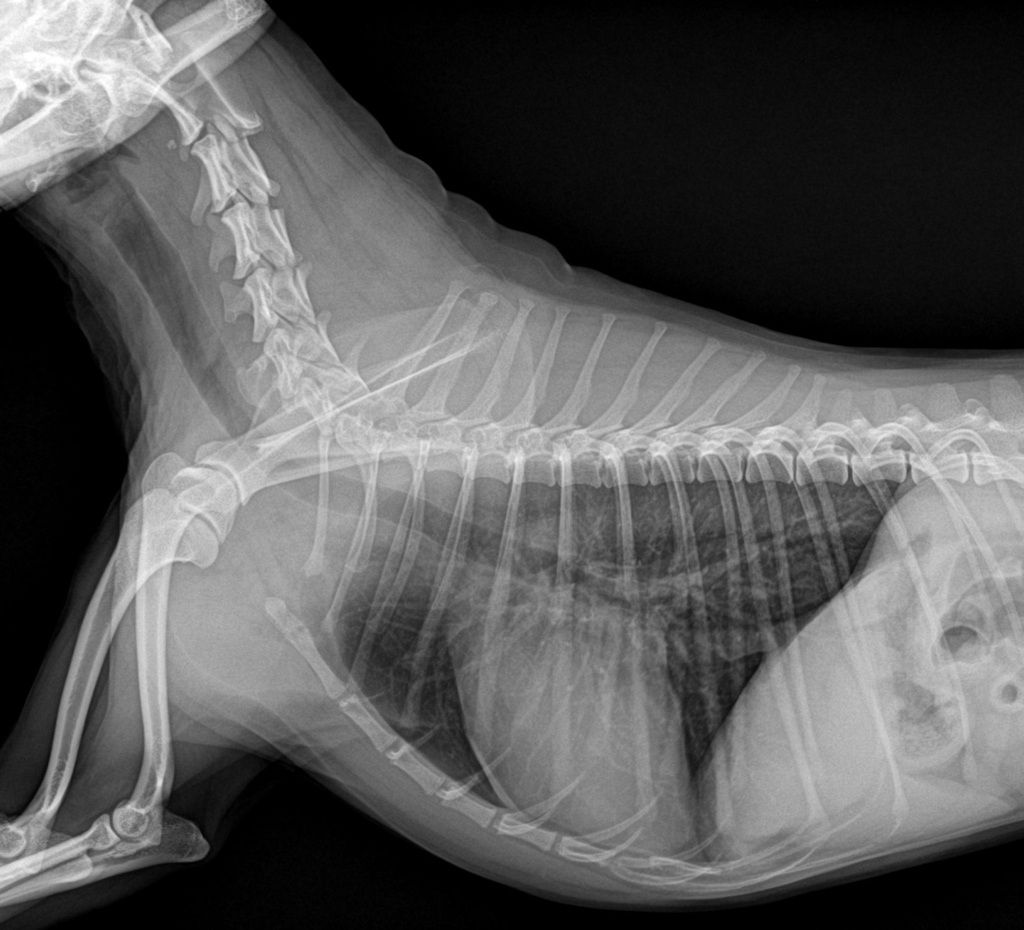

엑스레이상으로 목/허리디스크 확인이 가능한가요?

강아지가 특정부위가 아파서 엑스레이를 찍어봤는데 그렇게 심하지 않으면 엑스레이로는 알수가 없다고 하더라구요 ㅠㅠ.. 보실때 혹시 목이나 허리에 디스크는 보이지 않으신가요😭

디스크를 진단하는 golden standard 검사는 MRI, 검사입니다.

엑스레이는 척추의 골절이타 탈구, 융해성 병변 등 디스크 질환을 유발할 수 있는 몇몇 원인에 대한 감별 평가만 가능한 수준이라고 보아야 하지요.

때문에 엑스레이로는 디스크 여부를 평가해서는 안됩니다.